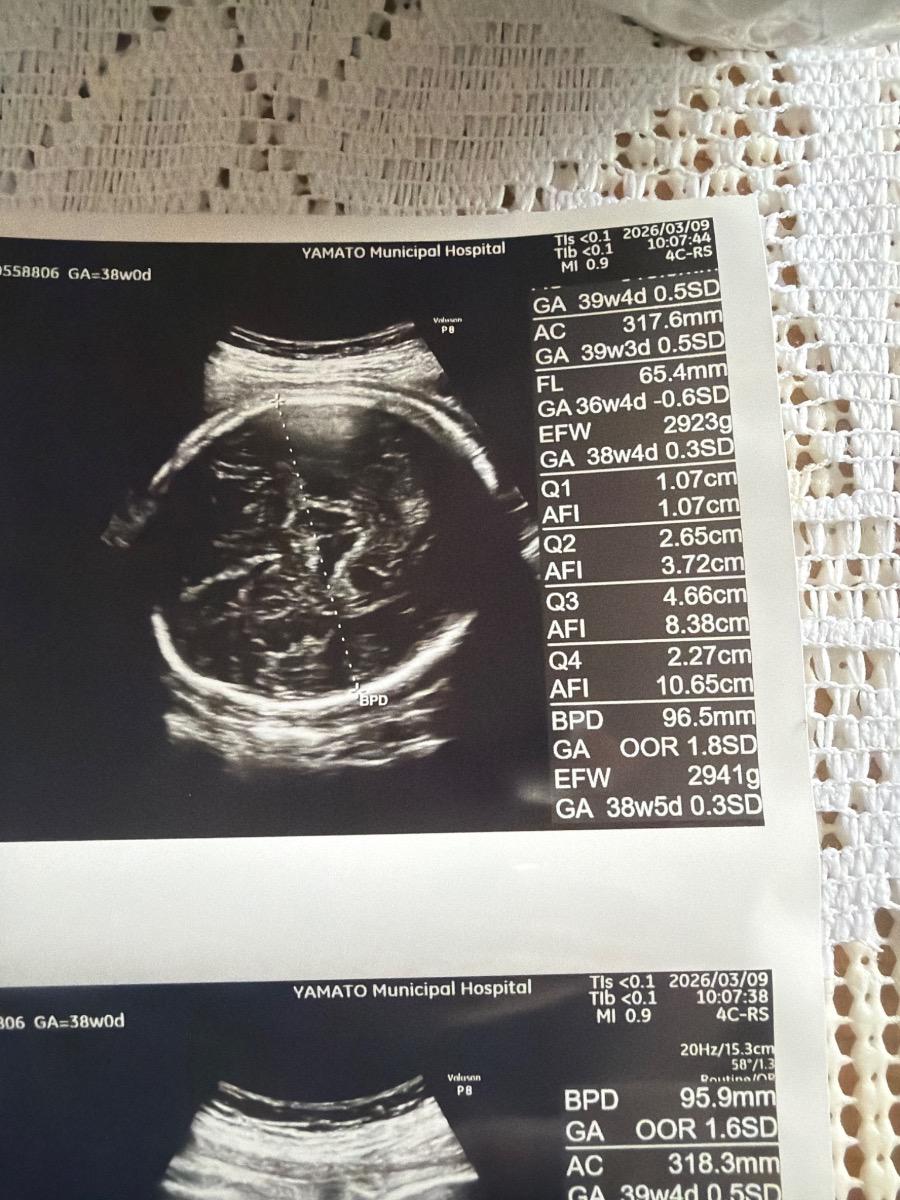

Thai 38 tuần FL nhỏ

Em đang bầu 38 tuần FL của bé hơi nhỏ hơn so với bình thường thì có đáng lo không ạ